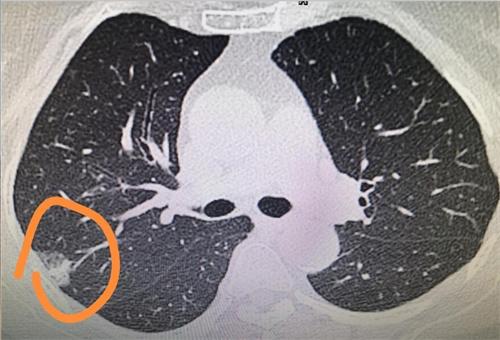

有位病人患有肺結節,當時并沒有繼續復查,過了一年復查后發現小細胞肺癌。這一個病例中病人65歲,有20年左右吸煙的歷史, 目前已經戒煙超過20年了 在2020年7月時進行體檢,發現有肺結節,后續通過增強CT等一系列檢查考慮良性結節。2021年11月份再次復查后,發現有結節增大,于是做了手術,在手術當中發現有小細胞肺癌,縱隔淋巴結考慮轉移,醫生診斷是小細胞肺癌廣泛期。

對于這樣的病例聽起來極為心痛,50歲以上的人群如果發現自身患有肺結節,特別是肺結節是大于1cm的,呈實體性質通常隨訪是三個月左右,除非高度懷疑就是良性的結節可以延長到一年時間,不然絕對不可以一年再隨訪。

小細胞肺癌是極為兇險的肺癌,預后效果也很差,根據現在獲得的數據,如果這個結節是小細胞肺癌,倍增時間1~2個月時間,生長速度是極快的,非常容易有轉移。